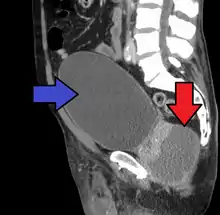

Abscess of the prostate (red arrow) resulting in urinary retention (blue arrow)

Acute prostatitis is relatively easy to diagnose due to its symptoms that suggest infection. The organism may be found in blood or urine, and sometimes in both.[2] Common bacteria are Escherichia coli, Klebsiella, Proteus, Pseudomonas, Enterobacter, Enterococcus, Serratia, and Staphylococcus aureus. This can be a medical emergency in some patients and hospitalization with intravenous antibiotics may be required. A complete blood count reveals increased white blood cells. Sepsis from prostatitis is very rare, but may occur in immunocompromised patients; high fever and malaise generally prompt blood cultures, which are often positive in sepsis. A prostate massage should never be done in a patient with suspected acute prostatitis, since it may induce sepsis. Since bacteria causing the prostatitis is easily recoverable from the urine, prostate massage is not required to make the diagnosis. Rectal palpation usually reveals an enlarged, exquisitely tender, swollen prostate gland, which is firm, warm, and, occasionally, irregular to the touch. C-reactive protein is elevated in most cases.[4]

Severely ill patients may need hospitalization, while nontoxic patients can be treated at home with bed rest, analgesics, stool softeners, and hydration. Men with acute prostatitis complicated by urinary retention are best managed with a suprapubic catheter or intermittent catheterization. Lack of clinical response to antibiotics should raise the suspicion of an abscess and prompt an imaging study such as a transrectal ultrasound (TRUS).[7]